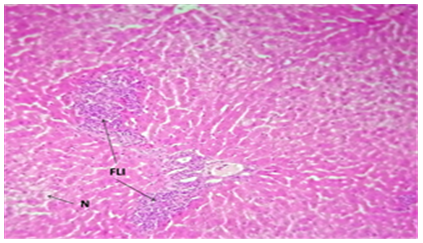

3.6 Microscopic analysis of liver tissue

The liver tissue's microscopic examination exposed evidence of hemorrhage and hemolysis, alongside significant inflammatory cell infiltration around the portal vein. A notable presence of macrophages (Kupffer cells) within the sinusoids was also observed. Moreover [33], fatty necrosis was prevalent in a majority of hepatocytes, highlighting the protective and reparative roles of chitosan against liver damage induced by stress factors and possibly by the metabolic disturbances associated with fungal infections, as shown in Figures 4-9, which starkly contrast the findings in the control group.

Figure 9. The histological slice of the liver treated with Nystatin and C. Krusei revealed: FLI) focal lymphocytic infiltration in the portal area. N) Some necrotic cells are observed